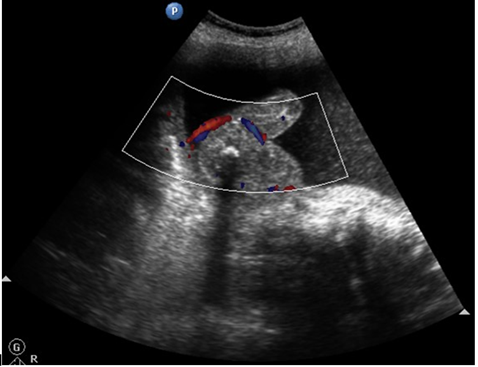

The incidence of the TRAP sequence is estimated as 1% of monozygotic twins, affecting 1/35,000 to 1/50,000 births.1 Most of the cases of TRAP sequence are seen in twins, with only 8% in triplets. The risk increases with multiple pregnancies of higher order.2 Twin reversed arterial perfusion (TRAP sequence) represents a syndrome characterized by partial or complete lack of cardiac development in one of the twins and abnormal vascular communication in the placenta.3 In our case, we had monochorionic triplets with TRAP physiology, which is very rare (Figure 1).

In the TRAP sequence associated with twins, the normal twin ‘pumps’ blood to the abnormal twin, called the ‘recipient’ twin, through abnormal artery-to-artery and venous-to-venous communications in the placenta. This is in conjunction with the vascular anastomosis, which takes place in TRAP syndrome.4 (Figure 2 - Figure 7).

Prenatal diagnosis by ultrasound is suspected when there is discordance, and bizarre malformations suspected in a twin gestation presents with retrograde blood flow in acardiac twin demonstrated by pulsed/colour flow Doppler.7,8